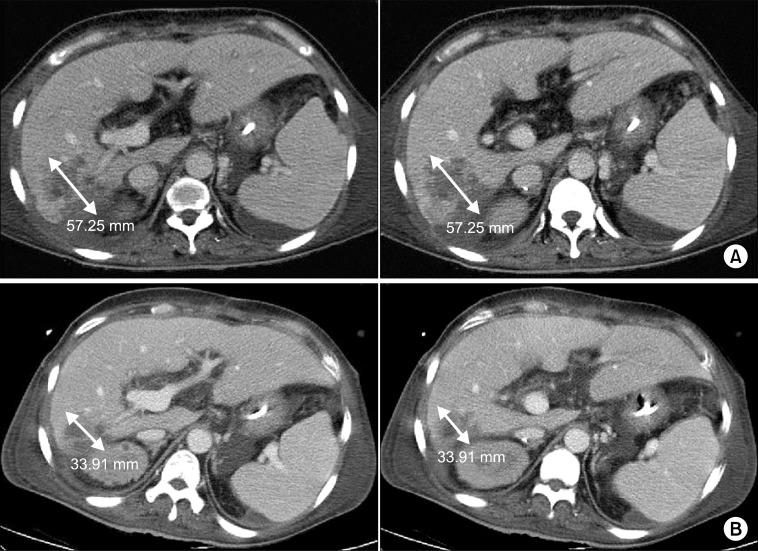

It is important that extrahepatic arteries are identified precisely at the time of graft procurement. We present a case where the accessory right hepatic artery of the liver was ligated leading to postoperative liver abscess formation in the liver graft. A forty-seven-year-old female patient diagnosed with liver cirrhosis underwent orthotopic cadaveric liver transplantation due to altered mentality. The donor graft showed a variant of the hepatic artery anatomy where an accessory right hepatic artery arose from the superior mesenteric artery. This artery was accidentally transected during procurement. Since the back bleeding test using perfusion fluid was good, the artery was ligated. Postoperative abdominal computed tomography scan revealed a 6 cm low attenuating lesion in the liver. The patient underwent conservative treatment. We believe that even small accessory arteries (1 to 2 mm) should be reconstructed whenever possible to avoid postoperative complications such as liver abscess.

在获取移植物时精确识别肝外动脉非常重要。我们报告一例病例,肝脏的副右肝动脉被结扎,导致肝移植术后肝脓肿形成。一名47岁诊断为肝硬化的女性患者因意识改变接受了原位尸体肝移植。供体移植物显示肝动脉解剖结构变异,一条副右肝动脉发自肠系膜上动脉。在获取过程中该动脉意外被切断。由于使用灌注液进行的回血试验良好,该动脉被结扎。术后腹部计算机断层扫描显示肝脏有一个6厘米的低密度病变。患者接受了保守治疗。我们认为,只要有可能,即使是小的副动脉(1至2毫米)也应进行重建,以避免术后并发症如肝脓肿。